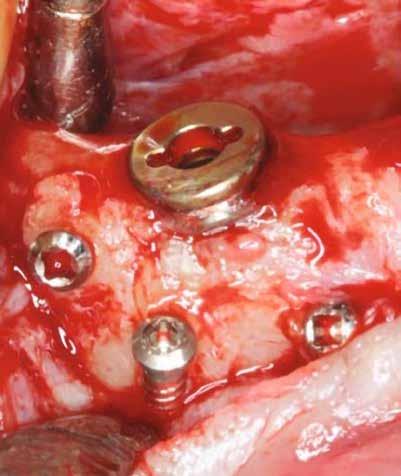

horizontális metszéssel kötöttük össze (2–5. ábra). A metszések hosszát és a köztük lévő távolságot minden esetben a lágyszövet augmentációhoz szükséges keratinizált szövet határozza meg. A lebeny deepitelizációját egy 15C-s szikepengével végeztük (6. ábra). Ezt követően félvastag lebenyt preparáltunk (7. ábra). A lebenyt apikálisan, az alapjáról belső, felületes metszéssel felszabadítottuk, hogy passzívan áthelyezhessük és rögzíthessük, feszülés nélkül. Meziális irányba 180 fokkal átforgattuk (8–9. ábra). A meziális papillát alagúttechnikával (tunnelling technique) készítettük elő a graft befogadására (10. ábra). Az így kialakított lebenyt a recipiens ágyban rögzítettük az újonnan kialakított vesztibulum alapjánál 5-0 nem felszívódó PTFE (Coreflon, IMPLACORE) varratokkal. A graftot behajtottuk az ínyszél alá és meziális oldalon rögzítettük PTFE varratokkal (11–14. ábra) A műtétet követően napi kétszeri, 0,12%-os klórhexidin tartalmú szájvízzel történő öblögetést javasoltunk a páciensnek, két héten keresztül. Gyulladáscsökkentésre 8 óránként 400 mg Ibuprofént javasoltunk, három napon keresztül. A páciens elmondása szerint sem fájdalmat, sem különösebb diszkomfortot nem tapasztalt. Ezt követően, további 4 héten keresztül, 0,2%-os klórhexidin tartalmú szájvízzel történő öblögetést javasoltunk a betegnek és instruáltuk, hogy lehetőleg ne mossa fogkefével az érintett területet. A varratokat egy héttel később távolítottuk el. A donor és a recipiens terület – 10 nappal a műtétet követően – kiválóan gyógyult (15–16. ábra). Az ezt követő kontrollokat a következő időpontokban ejtettük meg: kettő, illetve négy héttel a műtét után, majd három, hat és tizenkét hónappal később, ezt követően pedig félévente (17–20. ábra). Minden kontroll alkalmával professzionális fenntartó kezelést végeztünk a területen.

11. ábra: A Kígyó lebeny (varratok disztális részén).

12. ábra: A graftot a meziális oldalon rögzítettük PTFE varrattal.

13. ábra: A graft az ínyszél alá húzva.

14. ábra: Közvetlenül a műtét utáni kép, az utolsó öltések lenyomják a lebenyt, hogy ne maradjon szabad terület.